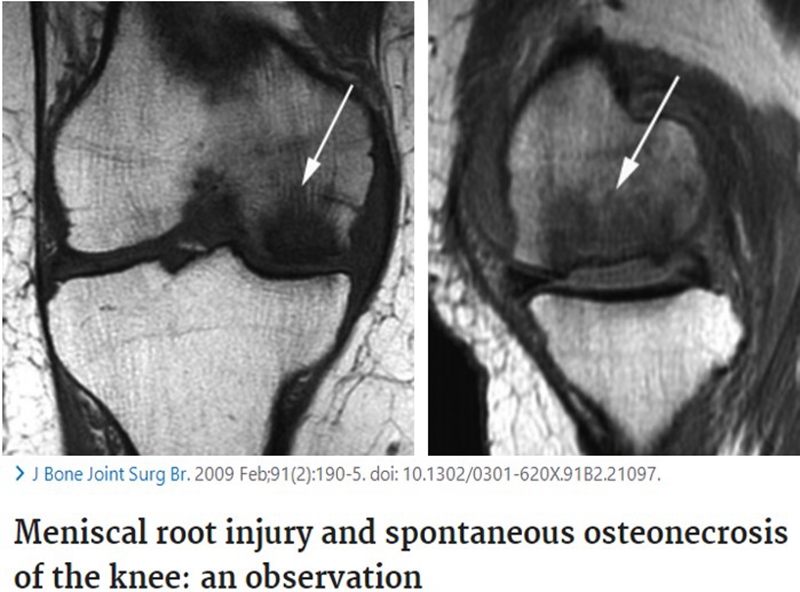

SONK与内侧半月板后根部损伤,有国外学者在SONK患者中通过MRI及关节镜检查,常可发现合并内侧半月板后根部的撕裂,该发生率可达到80%(24/30), 15例完全撕裂,9例部分撕裂。结果表明SONK可能与内侧半月板后根部撕裂后,导致股骨负重区的应力集中、软骨下骨髓水肿有关。

对于半月板损伤类型对SONK的影响,一项研究结果显示内侧半月板后根部撕裂组的半月板突出率为46.1%,平均坏死面积为423.1mm2。内侧半月板后角水平裂组的半月板突出率为35.3%,平均坏死面积为175.8mm2。

与内侧半月板后角水平撕裂相比,后根撕裂将导致更大程度的突出和更广泛的骨坏死。

SONK与内侧半月板突出的相关研究中,100%(104)SONK中都有半月板突出,4个SONK在发病前因膝关节疼痛体检发现半月板突出,几个月后通过MRI检查显示存在 SONK。

研究证明半月板挤压是SONK的发病机制之一,半月板挤压的进展可能与SONK的发展有关。